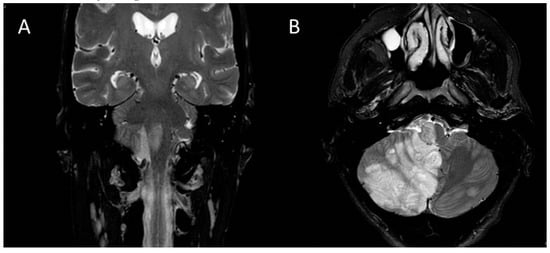

Therapy of Dysphagia by Prolonged Pharyngeal Electrical Stimulation (Phagenyx) in a Patient with Brainstem Infarction

2. Case Report